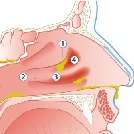

Snot

Snot kan er op veel manieren uitzien. Snot zegt soms iets over de oorzaak van de neusaandoening. Er kan een onderscheid gemaakt worden tussen helder, wit, geel, groen, rood, bruin en zwart snot.